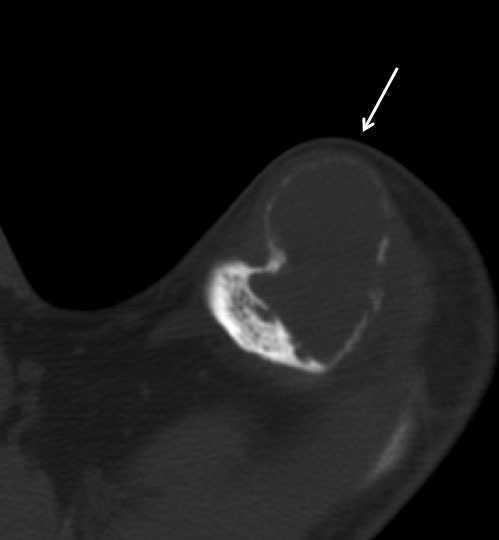

Presentamos el caso de un varón de 38 años con insuficiencia renal crónica terminal secundaria a nefropatía por reflujo, en programa de hemodiálisis desde los 23 años. Presentaba hiperparatiroidismo secundario tratado con paricalcitol por intolerancia digestiva a cinacalcet, con hormona paratiroidea (PTH) en torno a 1900 pg/ml. Consultó por una tumoración indolora, dura y sin signos inflamatorios, de un mes de evolución en el hombro izquierdo (figura 1). La serie ósea (figura 2 y figura 3) y la tomografía axial computarizada cérvico-torácica (figura 4) mostraron una imagen ovoidea, hipodensa y de borde no escleroso en la diáfisis de la tibia derecha y lesiones osteolíticas expansivas, con importante adelgazamiento de la cortical en las zonas distales de ambas clavículas, la mayor (4 cm de diámetro) en el lado izquierdo, que corresponden a tumores pardos debidos al hiperparatiroidismo secundario. Se realizó una paratiroidectomía total, observándose adenomas en las glándulas izquierdas y descenso inmediato de la PTH hasta 0,3 pg/ml.

Figura 3. Imagen de radiografía de tórax en la que se aprecian tumores pardos en ambas clavículas